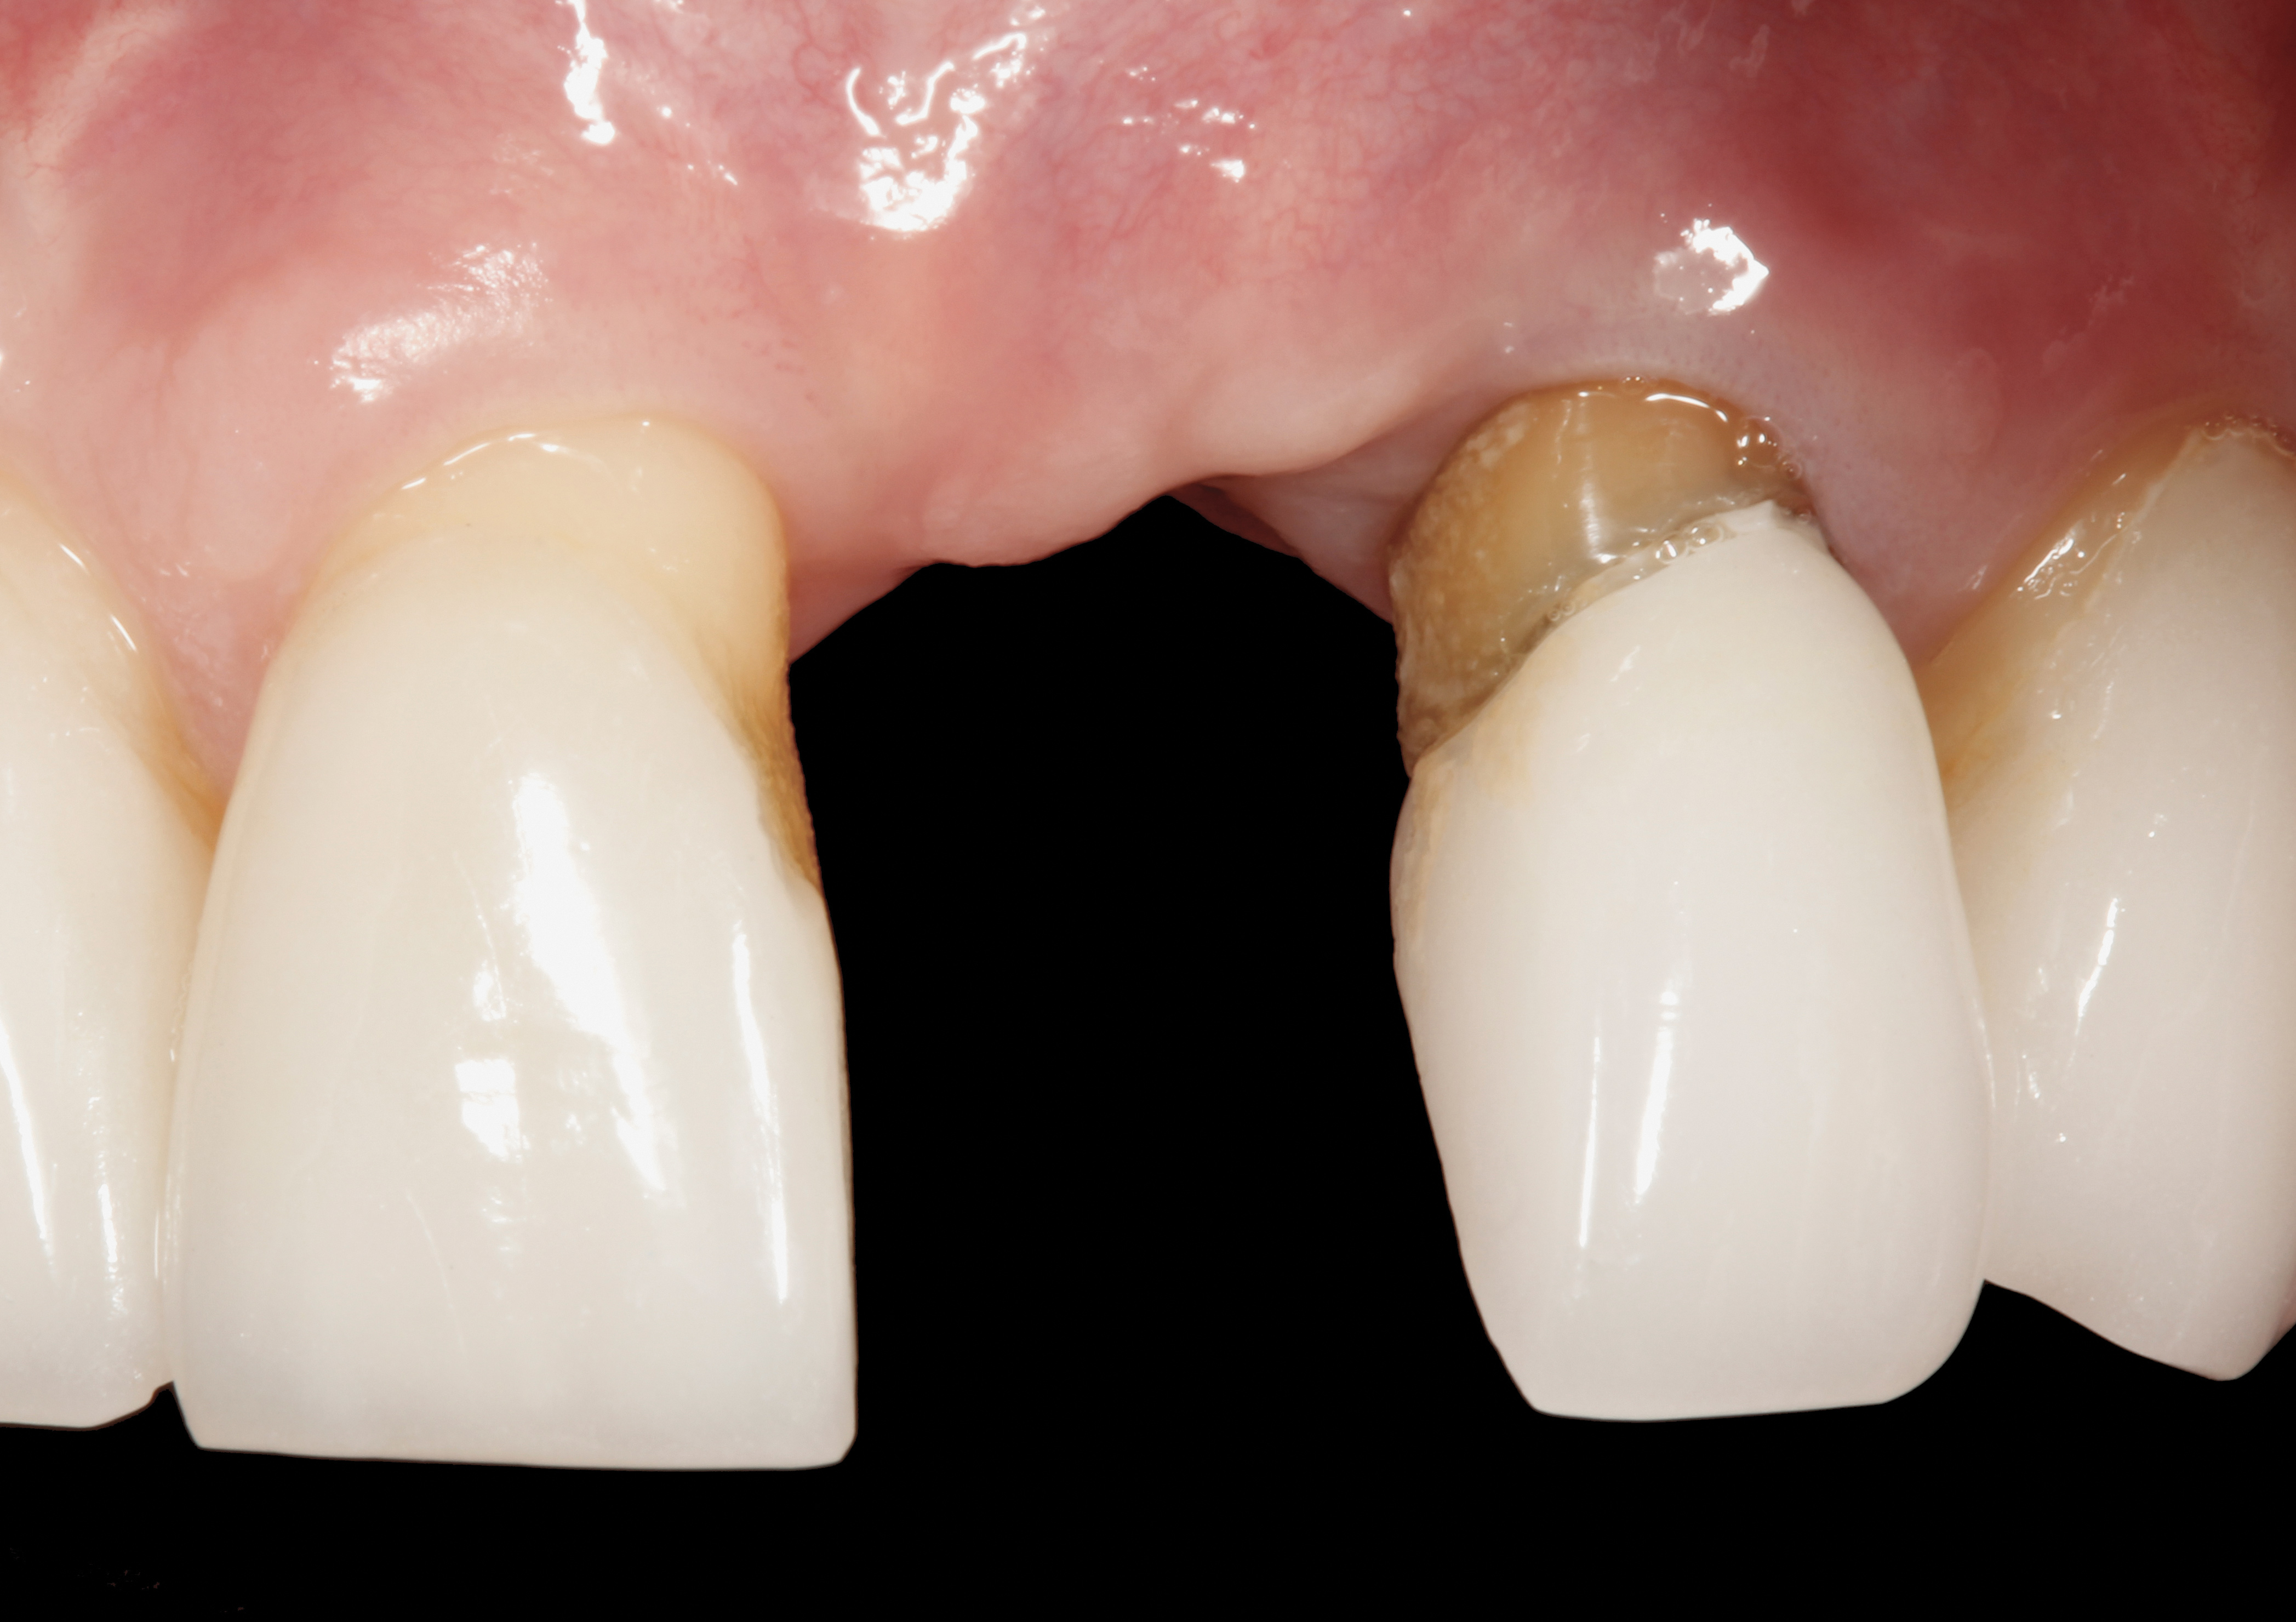

Problem: The implant is placed too facial with significant recession on the midfacial aspect of the abutment and/or crown; the implant is healthy and the patient has a high smile line with an intermediate to thick periodontal phenotype (Figure 1 and Figure 2).17-19

Fig 1. Midfacial recession can affect the esthetics of a smile and lead to an unsatisfactory outcome.

Fig 2. The cause for midfacial recession is excessive labial implant placement. Secondary to poor placement is overcontouring of the implant abutment.

Fig 3. A patient presented with a high smile line and midfacial recession of the maxillary right lateral incisor as evidenced by the increased tooth length compared with the contralateral lateral incisor.

Fig 4. Intraoral view of tooth No. 7 with the gingival zenith more apical than the adjacent central incisor and canine tooth.